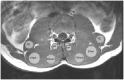

Objective: To investigate differences in diffusion tensor imaging (DTI) parameters and proton density fat fraction (PDFF) in the spinal muscles of younger and older adult males.

Methods: Twelve younger (19-30 years) and 12 older (61-81years) healthy, physically active male participants underwent T1W, T2W, Dixon and DTI of the lumbar spine. The eigenvalues (λ1, λ2, and λ3), fractional anisotropy (FA), and mean diffusivity (MD) from the DTI together with the PDFF were determined in the multifidus, medial and lateral erector spinae (ESmed, ESlat), and quadratus lumborum (QL) muscles. A two-way ANOVA was used to investigate differences with age and muscle and t-tests for differences in individual muscles with age.

Results: The ANOVA gave significant differences with age for all DTI parameters and the PDFF (P < .01) and with muscle (P < .01) for all DTI parameters except for λ1 and for the PDFF. The mean of the eigenvalues and MD were lower and the FA higher in the older age group with differences reaching statistical significance for all DTI measures for ESlat and QL (P < .01) but only in ESmed for λ3 and MD (P < .05).